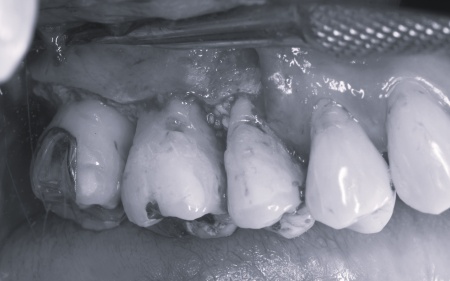

インプラント治療は、周囲の歯を削ることなく失った歯の部分のみを単独で補うことができます。 ただし、外科手術が必要となり治療期間が比較的長くなる点がデメリットです。 次に歯周病が認められるその他の奥歯については、歯周組織再生療法を行いできるだけ歯を抜かずに残す方法を提案しました。

さらに虫歯が再発していた左上奥歯については、虫歯をしっかりと取り除いたうえで被せ物による修復治療を提案しました。 それぞれのメリット・デメリットを丁寧に説明したところ、治療計画に同意いただきました。 まず、歯周基本治療から開始しました。 下左右の第1大臼歯を抜歯し、その部位にインプラントを埋め込む手術を行いました。同時に、インプラントの隣にある下の第2大臼歯に対して歯周組織再生療法を施しています。 また、左上の奥歯は虫歯を取り除いたあと、歯の形を整えて型取りを行い、最終的にジルコニアクラウンを装着しています。 段階的に治療を進め、すべての治療を終了しました。 |